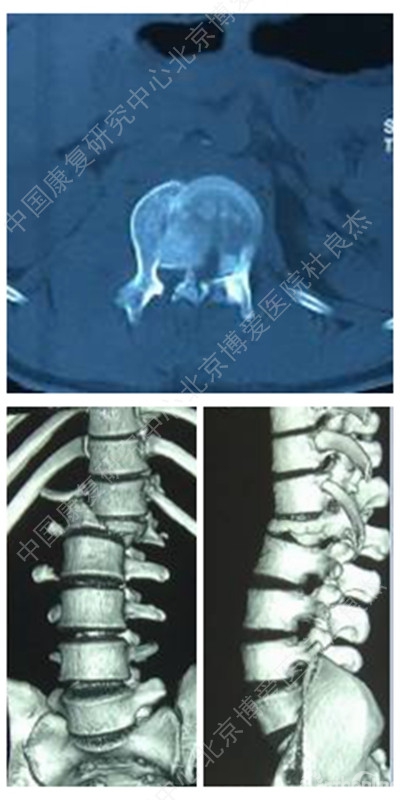

CT及三维重建